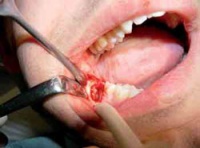

Diese Arbeit präsentiert erstmals eigene klinische und histopathologische Befunde zu Schleimhautveränderungen im Zusammenhang mit Snus-Konsum. Zudem werden dentale und parodontale Auswirkungen wie Zahnverfärbungen, Abrasionen, Karies, Gingivitis und Parodontitis beschrieben. Histologisch zeigte sich eine Entwicklung von reaktiver Gingivitis bis hin zu submuköser Fibrose, insbesondere an der bevorzugten Applikationsstelle im Vestibulum maxillare.